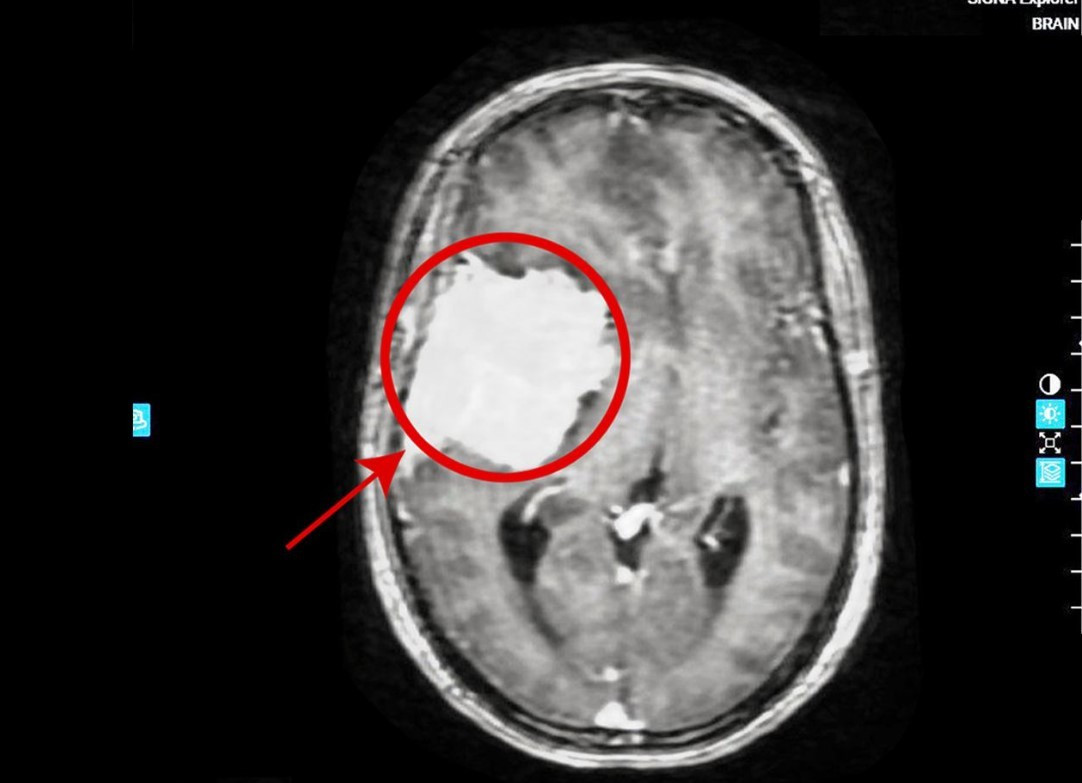

Chị Trang (45 tuổi) đau đầu kéo dài nhiều ngày tưởng do tiền đình nên chủ quan không đi khám. Gần đây triệu chứng đau đầu tiến triển nặng kèm méo miệng, suy giảm ý thức… Người bệnh tới Bệnh viện Đa khoa Tâm Anh khám phát hiện khối u não kích thước 5x7 cm ăn mòn xương sọ, đẩy lệch đường giữa não.

Khối u khổng lồ trong não người bệnh - Ảnh BVCC

TS.BS Nguyễn Đức Anh, Trưởng khoa Ngoại Thần kinh Cột sống, Bệnh viện Đa khoa Tâm Anh Hà Nội chỉ định người bệnh chụp MRI phát hiện khối u não: Kích thước 5x7 cm; Ăn mòn xương sọ, đè đẩy sâu vào cấu trúc não; Làm lệch đường giữa tới 10mm sang bên đối diện.